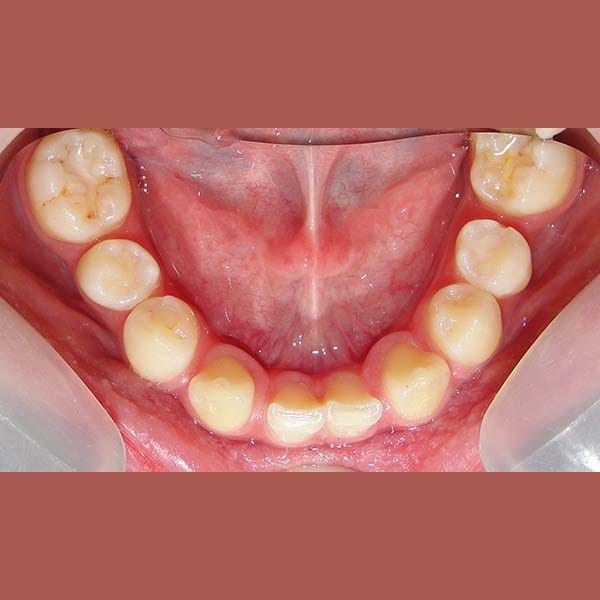

عانت هذه السيدة من وجود عضة عميقة أمامية و غياب خلقي لسنين أماميين سفليين ،بالإضافة لتراكب و عدم ارتصاف الأسنان الأمامية العلوية بشكل جيد – تم فتح مسافة كافية لوضع غرستين سنيتين و تم تصخيح العضة العميقة تقويمياً